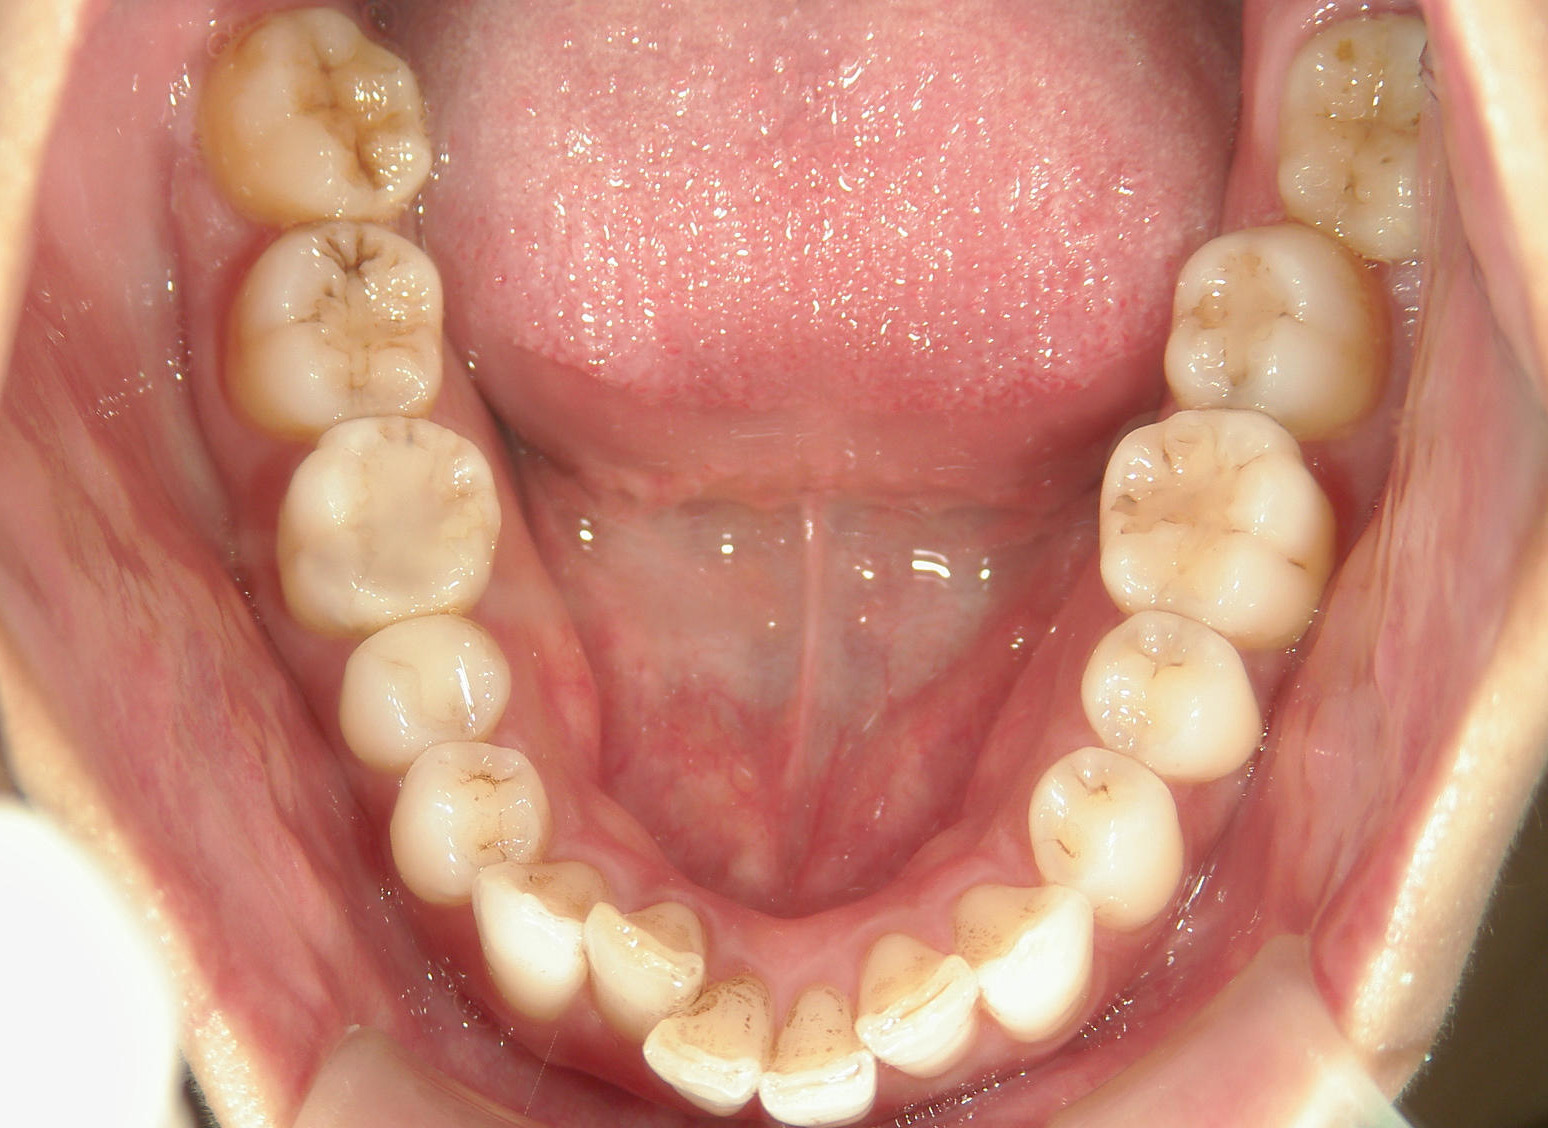

全顎ワイヤー矯正 症例(82)

主訴: 前歯の歯並びが気になる。

上下左右 第一小臼歯(4本)、左右上 親不知(2本)を抜歯。

ミニインプラント、アップライトスプリングを併用。

矯正前に左右上前歯4本を仮歯に変え、矯正治療後にセラミック(SHT)に冠せなおしました。

カテゴリー : ガタガタ(叢生)